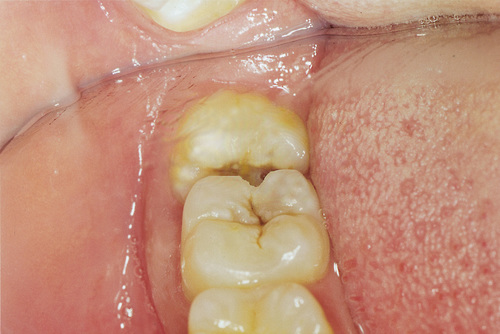

Pericoronitis is the inflammation of the gums above and around the tooth due to the overlying gum flap that causes chronic inflammation. This will result in a throbbing recurrent pain that will only resolve with the removal of the wisdom tooth.